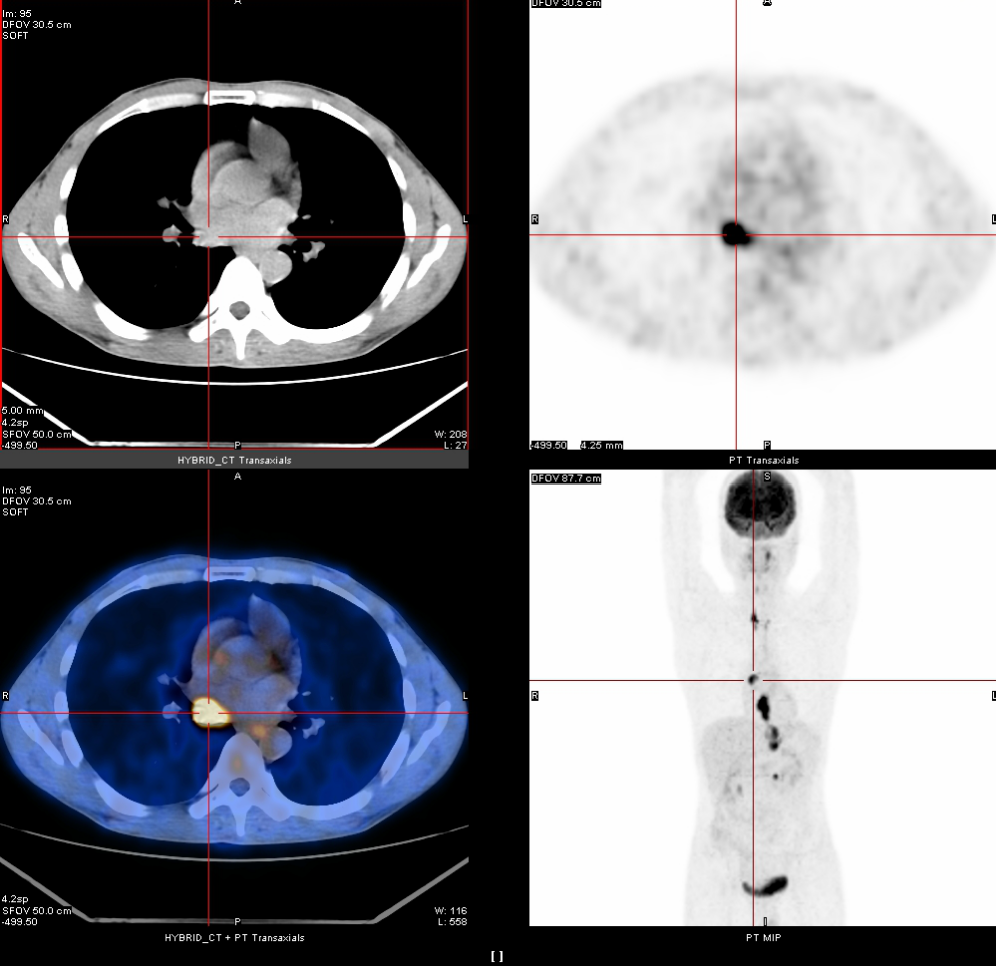

2020年3月13日

全身PET-CT示:1、食管胸中下段管壁不规则增厚,代谢增高,考虑食管癌。2、上纵隔胸廓入口区气管两旁、右下肺静脉后方、贲门区、肝胃间隙、降主动脉后方、膈肌脚后方、腹膜后腹主动脉左旁(左肾门下方平面)见多发高代谢肿大淋巴结,考虑淋巴结转移,建议随访复查。3、右肺上叶前段胸膜下小结节影,代谢未见增高,建议随访复查。4、右肺下叶外基底段条索影,考虑慢性炎性改变。5、双侧上颌窦轻度慢性炎症。6、双侧颈部多发小结节影,代谢未见增高,考虑淋巴结慢性炎性增生。7、肝左叶内侧段小钙化灶。